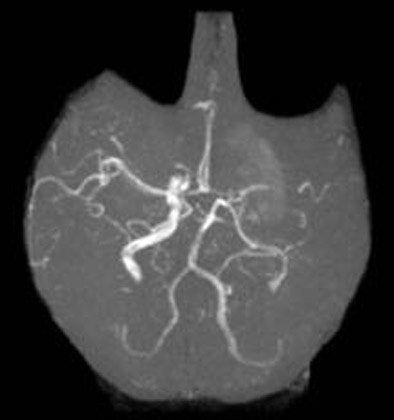

![]() |

| Three-dimensional time-of-flight angiography obtained at the time of admission shows an occlusion of the left distal M1. Image courtesy of Dr. Sotirios Bisdas. |